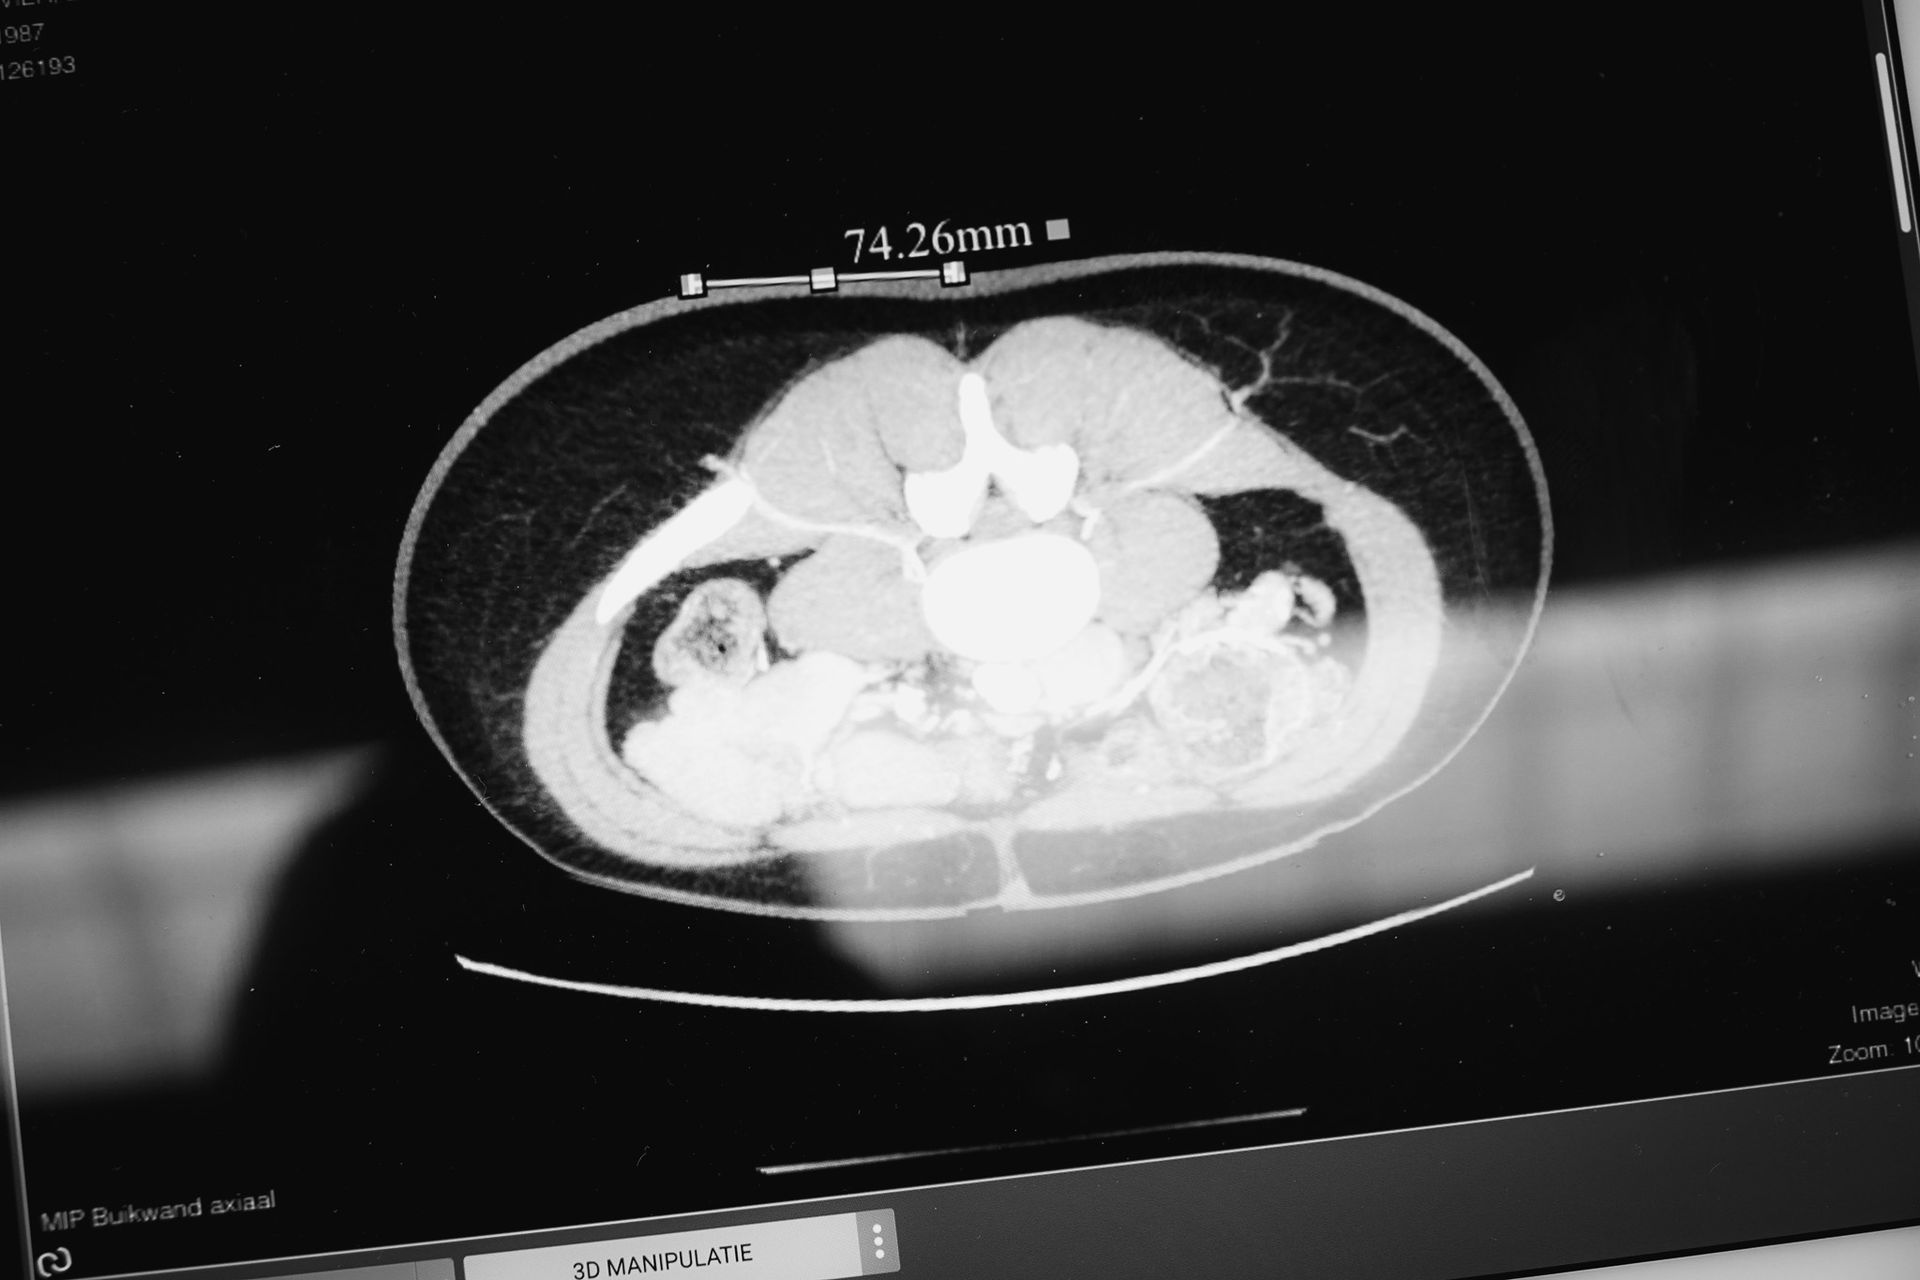

Bij een keuze voor de DIEP flap wordt een angio CT scan onderzoek uitgevoerd van de buikregio. Dit dient om de bloedvaten in kaart te brengen. Dit zorgt ervoor dat men een duidelijk beeld krijgt van het verloop van de bloedvaten, de kwaliteit van de bloedvaten en toont ook de ligging aan van de bloedvaten. Het vergemakkelijkt de ingreep en geeft de chirurg als het ware een "map" van de anatomie.